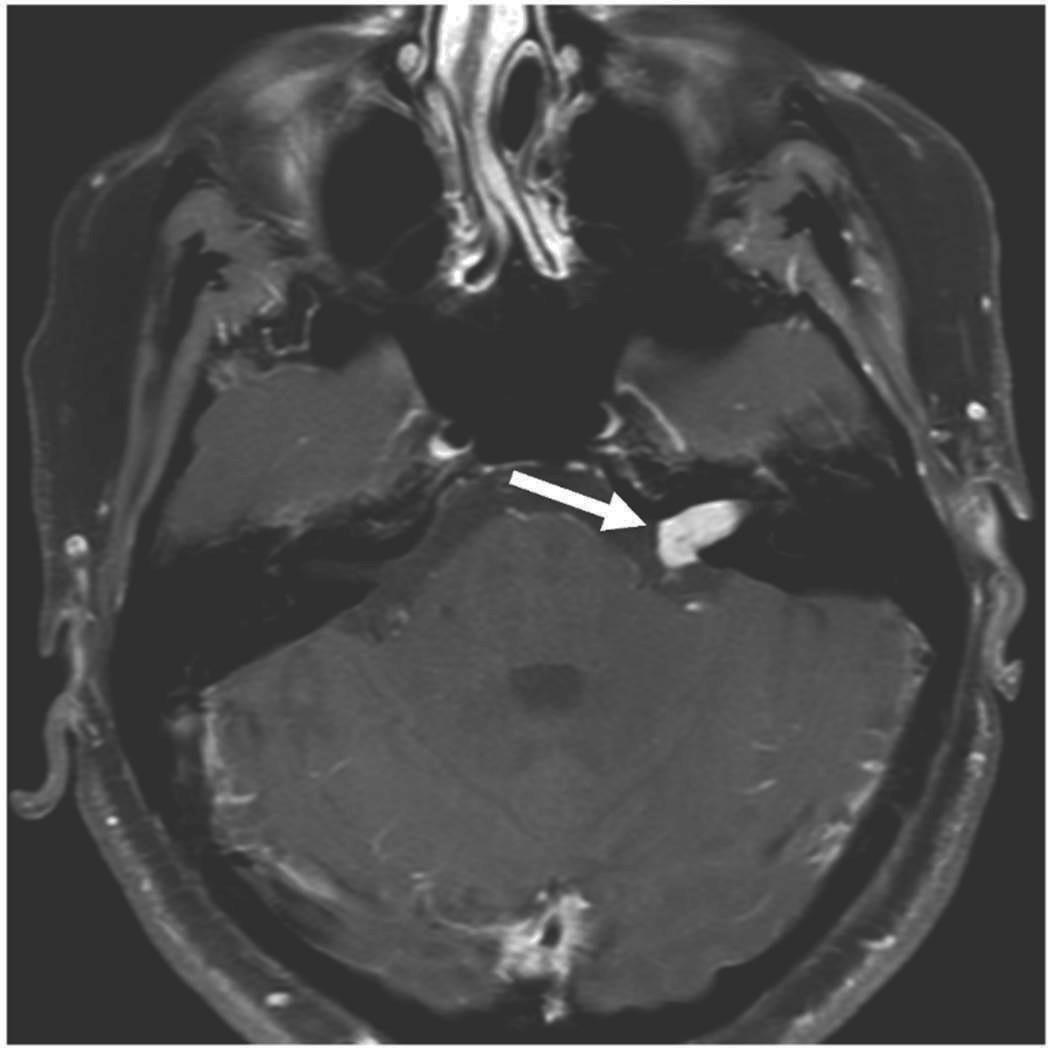

resonance images of various types of acoustic neuromas When Should An Acoustic Neuroma Be Removed Web most acoustic neuromas grow very slowly, although the growth rate is different for each person and may vary. Surgical approaches for removal of an acoustic tumor include: Web if you elect to have surgery for your acoustic neuroma, the approach should be a joint decision between you and your surgeon. Retrosigmoid approach (also known as the. Web approaches to. When Should An Acoustic Neuroma Be Removed.

Acoustic neuroma MRI wikidoc When Should An Acoustic Neuroma Be Removed Web approaches to acoustic neuroma surgery. Web some acoustic neuromas stop growing, and a few even spontaneously get smaller. Common symptoms include unilateral hearing loss and tinnitus. If there’s no change, patients. Web an average sized acoustic neuroma can be removed by an experienced surgeon in 30 to 45 minutes. Web if you elect to have surgery for your acoustic. When Should An Acoustic Neuroma Be Removed.